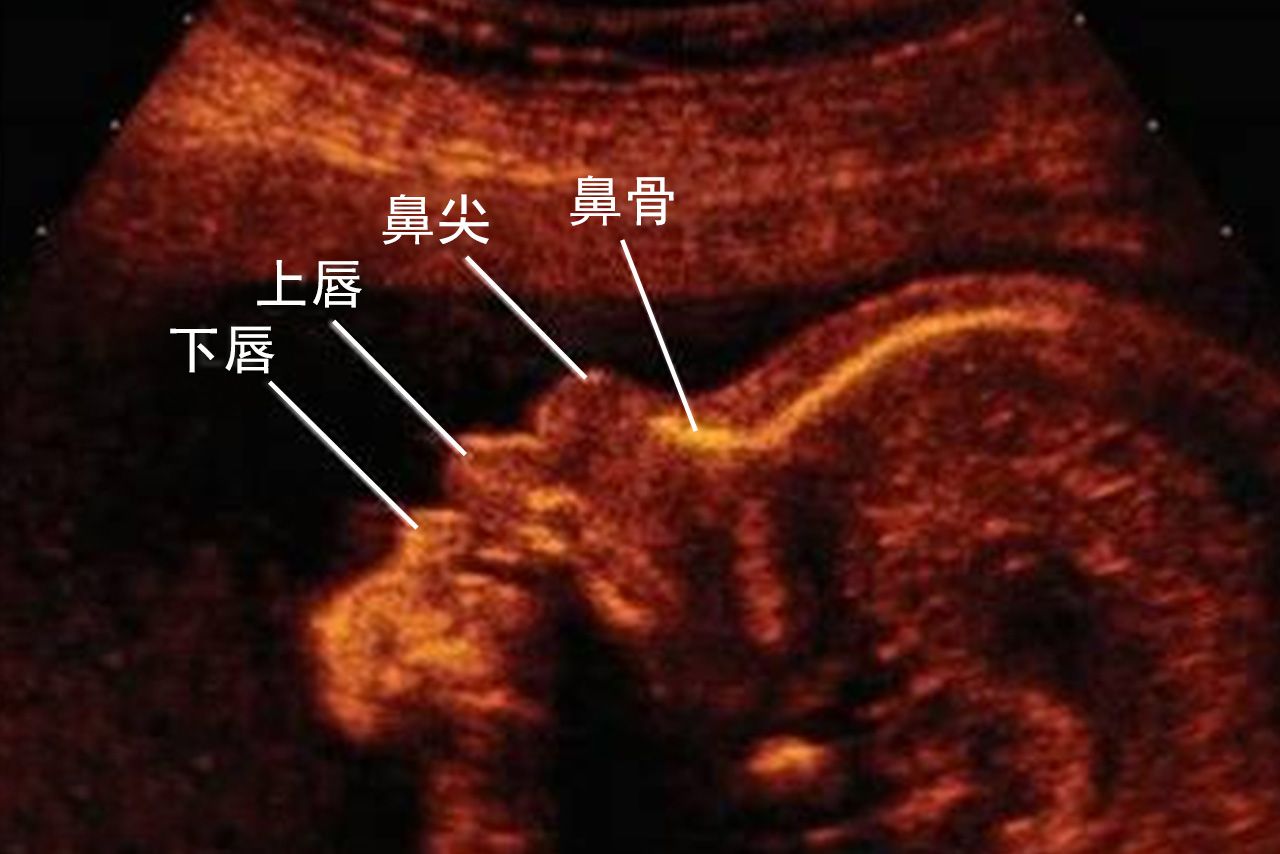

正常的胎儿鼻骨超声图像会出现三条清晰的线,如果是出现脑部发育不全及唇腭裂等异常情况,也会显示胎儿鼻骨超声异常。

胎儿颜面部形成主要在妊娠6~12周间。胎儿的鼻、唇、腭形成最晚,鼻、唇在11周能完全形成,腭到12周发育完全。通常在孕11~13+6周时进行鼻骨超声扫查。

检查鼻骨时超声图像应放大至只显示头部及上胸,取胎儿正中矢状面:前方显示鼻同时后方显示菱脑,胎儿鼻骨呈水平走向,探头声束垂直鼻骨与胎儿面部中轴线约成45度角。